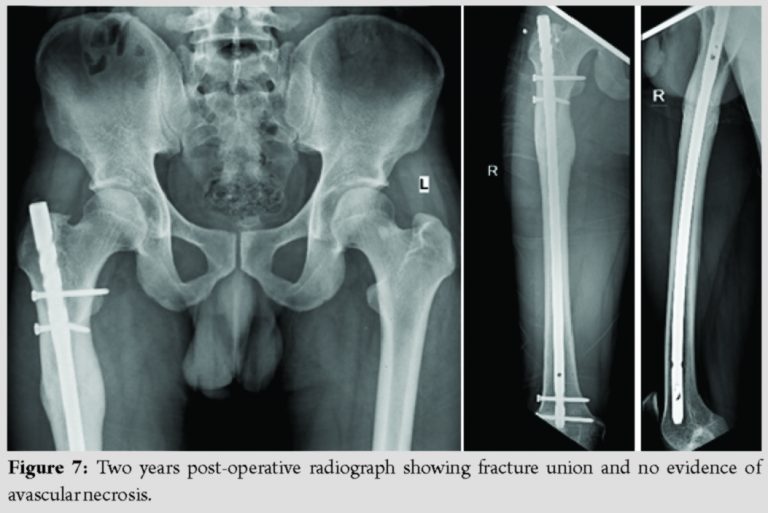

Radiological assessment was done at the time of 2 months (Fig. 5) and regularly until 2 years follow-up to check for fracture union and to rule out AVN of femoral head, secondary arthritis, and implant loosening.

At 2 years follow-up, Harris Hip Score was found to be 95 with no restriction of movements (Fig. 6) and fracture was united completely with no evidence of AVN and secondary osteoarthritis in the femoral head (Fig. 7).

Dislocation of hip is an orthopedic emergency which usually occurs due to high-energy trauma and it must be reduced as soon as possible (within 6 hours) to avoid complications such as avascular necrosis (AVN) and secondary osteoarthritis. Hip dislocations are usually associated with injury to femoral head, neck or shaft of femur, and acetabulum [8]. A posterior dislocation of hip associated with femoral head, neck, or shaft fracture is very unusual but not rare entity, but of that anterior hip dislocation with subtrochanteric femur fracture is very rare according to the literature support.The main peculiarity of our case is the anterior dislocation of the femoral head association with subtrochanteric femur fracture and the difficulty in the management of reduction of the hip and the treatment of the subtrochanteric fracture and its excellent clinical and radiological outcome after 2 years following the surgery. Addition to that, subtrochanteric femur fractures are very challenging due to its deforming force. Significant fracture displacement occurs due to the secondary pull of iliopsoas, gluteus medius, and short external rotators on the proximal fragment and pulls this segment into a position of flexion, abduction, and external rotation. Further, the unopposed pull of the adductors on the distal segment often leads to femoral shortening and adduction. These deforming forces need to be overcome in order to achieve an anatomical reduction. In our case, forceful abduction is the most important factor contributing to anterior dislocation with associated direct impact high-velocity injury leads to subtrochanteric femur fracture. Such injuries are orthopedic emergencies and require immediate surgical intervention. The biggest difficulty faced in this case is the need of achieving emergency reduction and the method of attempting closed reduction and maintaining reduction. The reason being that the proximal fragment cannot be reduced using the conventional reduction maneuvers described in literature, that as its discontinuity from the shaft cannot aid in its movement when the limb is pulled in traction. And that, the need of open reduction may cause an insult to the femoral head as it may require an incision to the anterior capsule in order to reduce the femoral head. The various studies in pertinence to anterior fracture dislocation of the hip are tabulated below. The main complications following this type of rare presentation usually will be avascular necrosis (AVN) of femoral head and secondary osteoarthritis usually more in patients with an ipsilateral neck as well as in old age. Thus, early reduction in the dislocated hip decreases the risk of AVN. A delay of more than 6 hours increases the risk of AVN from 10 to 40%. But However, we did not encounter this complication in our case at 2-year follow-up. Femoral head was reduced under GA and external fixator was applied temporarily to reduce the subtrochanteric fracture and then IMIL nailing was done on the second day. Non-weight-bearing mobilization was started from the 2nd post-operative day and then it was changed gradually into full weight-bearing walking at the end of 6 weeks. At 2 years follow-up after surgery, the radiographic assessment showed stable joint without any evidence of AVN and complete healing of fracture with good functional outcome with Harris Hip Score of 95.